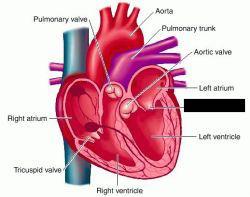

Anterior interventricular valve

Aortic Valve (=left semilunar)

Chordae tendineae

Coronary sinus

Endocardium

Epicardium

Left atrioventricular (=bicuspid, =mitral) valve

Left/right atrium

Left/right auricle

left/right ventricle

Myocardium

Papillary muscles

Pectinate muscles

Pulmonary trunk

Pulmonary valve (=right semilunar)

Right atrioventricular (=tricuspid) valve

Superior/inferior vena cava